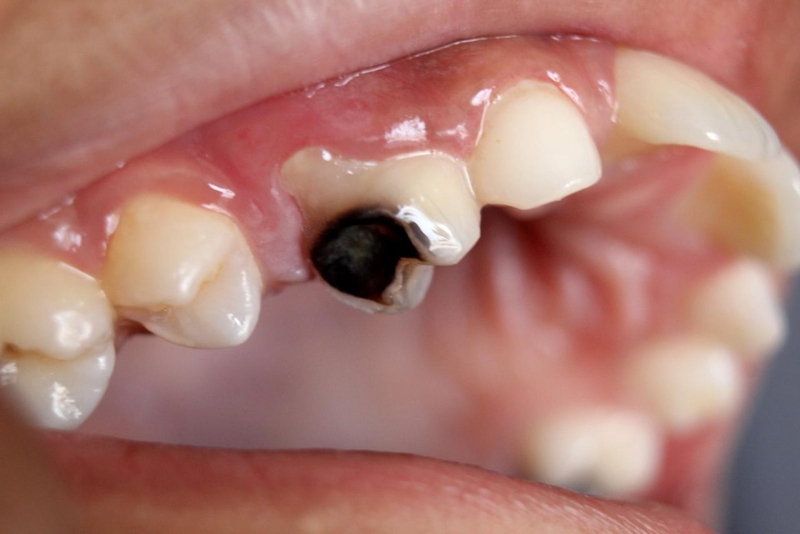

Sâu răng là tình trạng xảy ra khi tổ chức cứng của răng bị tấn công, tiêu dần đi và tạo lỗ trên mặt răng. Nếu không được điều trị kịp thời, tổ chức cứng của răng sẽ bị phá hủy nhiều hơn, ăn sâu xuống dưới và vào tủy răng dẫn đến sâu răng vào tủy. Răng bị sâu vào tủy có thể gây ra nhiều biến chứng ảnh hưởng đến sức khỏe răng miệng và toàn thân nếu không được điều trị kịp thời.

Sâu răng là tình trạng tổ chức cứng của răng bị tấn công, tiêu dần đi và tạo lỗ trên mặt răng

Khi sâu răng ăn vào tủy có thể sẽ khiến người bệnh cảm thấy đau nhức, khó chịu và ảnh hưởng đến việc ăn nhai, sinh hoạt hàng ngày. Một số dấu hiệu nhận biết như sau:

Trong hốc răng sâu thường sẽ có nhiều mảnh vụn thức ăn đọng lại kết hợp với vi khuẩn gây sâu răng tạo thành một ổ viêm. Khi tổ chức sâu răng chạm tới tủy sẽ gây viêm ở tủy răng gây đau. Tình trạng viêm có thể xảy ra ở cả buồng và tủy chân gây ra các cơn đau dữ dội.